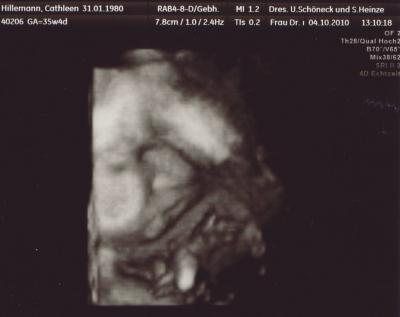

so, jetzt möchte ich auch mal wieder Bilder von meiner Maus zeigen - in 3D und es gab sogar ein Video sie ist knapp zeitgerecht entwickelt, ist halt immernoch ne zarte BPD 89,0 mm FOD 108,5 mm KU 311,4 mm AU 292,0 mm FL 68,1 mm geschätztes Gewicht bei 35+4: 2292 g

die Lady hatte leider nur die Nabelschnur vorm Mund, da hat auch alles schütteln und shaken nichts genützt